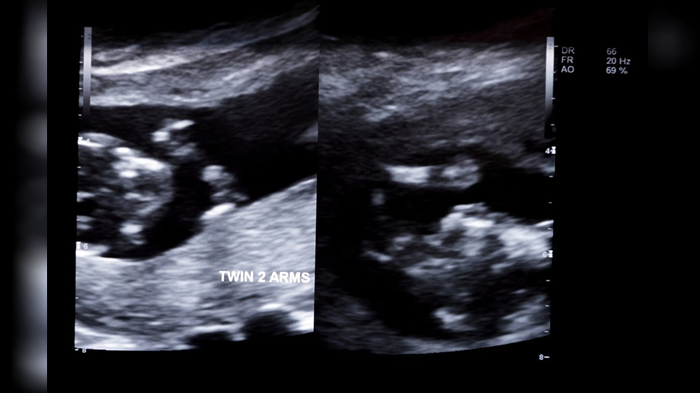

Bayi kembar (ilustrasi)

Bayi kembar (ilustrasi) (wittyfeed.com)